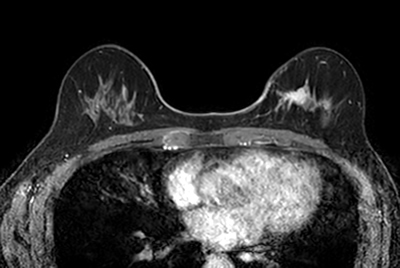

Breast Ca with T1 perfusion